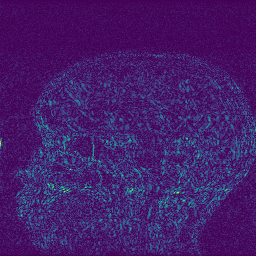

Edge preserving has always been a crucial concern in the design of reconstruction models. To improve the quality of reconstructed images and preserve image edges, some works suggested introducing edge priors in the original restoration problem to preserve image edges [4, 34]. However, they will suffer from complicated algorithm design and time-consuming training processes. Recently, some more efficient methods have been proposed to use edge maps as external guidance for image restoration. For example, Yang et al. [48] used off-the-shelf edge detectors to extract image edges from the degraded images. Fang et al. [12] predicted image edges by constructing an edge reconstruction network. Huang et al. [18] designed a novel dual discriminator GAN framework for solving fast multi-channel MRI, in which one GAN network is built for edge information enhancement. Inspired by these methods, we also consider introducing image edge prior as external guidance to MRI reconstruction since 1) image edges are prominent and distinguishable features in MRI (see Fig. 1), which can serve as a good guide to the model to recover high-frequency details; 2) the ground truth edges can be easily fetched via ordinary edge extraction operators, like Canny, Sobel, and Prewitt, which means that the edge maps can be learned in a data-driven manner. However, how to effectively utilize image edge priors to guide image reconstruction still remains a challenge. In some methods, edge information was simply concatenated with the input image and passed to the next stages. Though this is a simple way to utilize the edge priors, it may not give full play to the guiding role of the edge priors. Therefore, in this work, we want to explore a more efficient and effective mechanism to fully take advantage of image edge priors.

(a)

(b)

(c)

fastMRI is a large-scale MR dataset jointly established by Facebook AI Research and NYU Langone Health. It provides both knee and brain datasets for evaluation. In our work, we use the multi-coil knee dataset, which was acquired on three clinical 3T systems or one clinical 1.5T system using a 15-channel knee coil array. The dataset includes data from two pulse sequences, yielding coronal proton-density weighting with (PDFS) and without (PD) fat suppression. As is shown in Fig. 1, PD images usually contain more structural and prominent edge features than PDFS images, which suggests that it is more challenging to use edge guidance on PDFS datasets. Therefore, we explore the effectiveness of EAMRI on these two modalities. Following [13], for both PD and PDFS knee datasets, we separately filter out 227 volumes (8332 slices) for training and 24 volumes (1665 slices) for testing. The dataset is centrally cropped to .